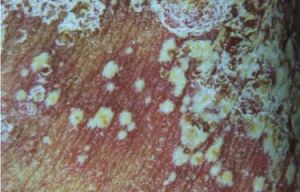

皮膚病變多先在肘部出現,以後發生在腿頭皮、腹和背部。80%的PA有指甲病變,而在銀屑病中僅30%,表現為指甲松離、凹陷、凸起、脫色和呈片段外觀。皮膚病變越嚴重,發生關節炎越多見。PA的關節病變有以下5種類型:①指和趾末端非對稱性單關節炎(5%~10%),常伴有關節臘腸樣改變和指甲病變;②慢性非對稱性單關節炎(50%~70%)同時累及2~3個關節;③與RA類似的慢性對稱性多關節炎(15%~25%),但RF呈陰性;④以骶髂關節炎為特徵的脊柱關節炎(20%~30%),男性多於女性,且與HLA-B27密切相關;⑤侵蝕性多關節炎,最少見的類型表現為骨質嚴重破壞畸形和關節僵直的多關節炎性改變,因多個指(趾)骨質破壞而出現“套疊”指,並可出現脊柱強直。和RA相比,PA是不太嚴重的疾病疼痛和功能障礙不常見。其他少見的病變是澱粉樣變性肺尖纖維變性和主動脈功能不全。偶爾出現小血管炎引起的皮膚膿皰病變健康搜尋。